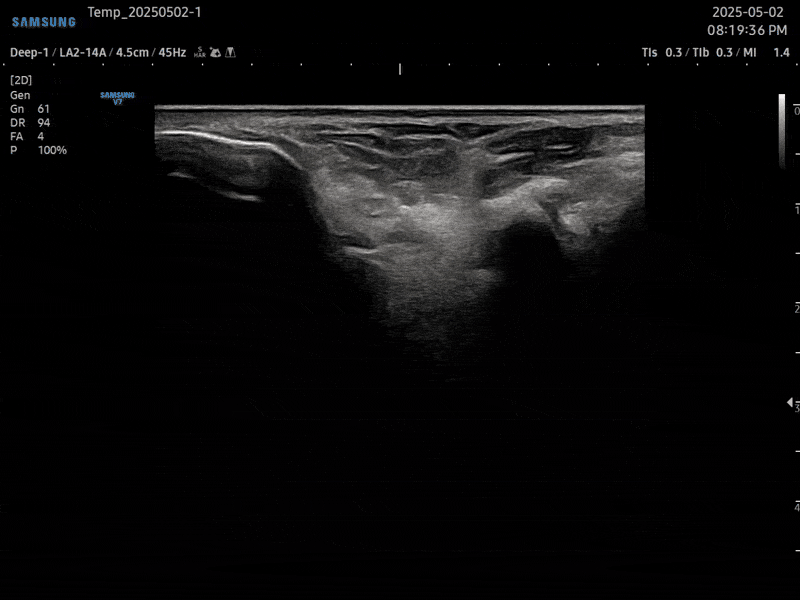

초음파 검사를 통해

발목 불안정증 통증의 직접적인

원인을 확인할 수 있습니다.

전후거비인대, 종비인대, 삼각인대를 진단하고

발목의 골관절염을 확인하여 맞춤 솔루션을 제공합니다.